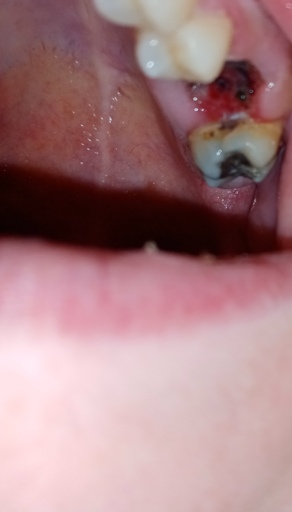

Wisdom teeth removed, is this dry socket or healing normally?

I’m concerned I have a dry socket from my salt rinses. Does this look like normal healing or is something wrong? It has a gray color and on the right side I can see some white. I got my teeth removed on 5/3 and felt like I was healing alright. I got...